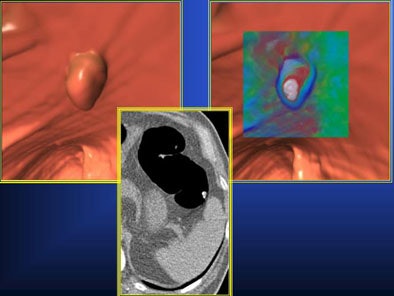

One possible way to reduce false positives and negatives in 3D is translucency rendering (TR) -- software that color maps minor differences in attenuation. Different colors (blue, green, red, and white) are assigned to areas of increasing attenuation, making it easier to distinguish the relatively homogeneous density of true polyps from more heterogeneous residual materials.

"3D translucency rendering is an accurate tool to easily differentiate true polyps from polypoid-like fecal residues during real-time 3D fly-through," he said. "However, unmarked fecal residues (FP calls) or opacified-coated true polyps (FN calls) may still be misinterpreted," necessitating the use of 2D confirmation in all cases. "So the purpose of the study was to evaluate the efficacy of translucency rendering for differentiating polyps from polyp-like residues," he said.

| Above, concentric circles and homogeneous interior of lesion depict the presence of a true polyp on translucency rendering software (Viatronix V3D Colon), shown with adjacent 2D correlations. Below, heterogeneous density of polypoid findings help identify residual fecal material. All images courtesy of Dr. Antonio Guerrisi. |